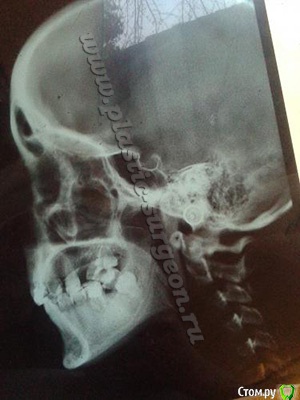

кристина1877 Опубликовано 12 июня, 2015 Автор Поделиться Опубликовано 12 июня, 2015 Кристина, прикус может быть одновременно и дистальным и глубоким. Точно диагноз ставится и план лечения составляется после расчета ТРГ (на вашем фото - снимок нечитаемый). Плюс у Вас множественные дефекты зубных рядов, смещения... Суть не в том как обозвать прикус и какой техникой лечить, а суть в том - что Именно Вы и Ваш врач планируете получить на выходе и каким способом. Посмотрите пожалуйста ТРГ, как думаете, можно ли обойтись без остеотомии? Ссылка на комментарий

Yana guapa Опубликовано 12 июня, 2015 Поделиться Опубликовано 12 июня, 2015 Кристина, а что именно Вы и Ваш доктор ожидаете от ОСТЕОТОМИИ??? что именно собираетесь изменять? Ссылка на комментарий

кристина1877 Опубликовано 12 июня, 2015 Автор Поделиться Опубликовано 12 июня, 2015 Кристина, а что именно Вы и Ваш доктор ожидаете от ОСТЕОТОМИИ??? что именно собираетесь изменять? Мне не нравятся мои губы. из- за того что прикус дистальный. верхняя губа больше(выступает) над нижней. это несимметрично выглядит.нет эстетики. консультировалась. у нескольких ортодонтов. одни говорят что брекетами можно все исправит ь и выдвинуть. другие- что нужна ортогнатическая хирургия...что скажете по снимку. есть несоответствие челюстей?) Ссылка на комментарий

Yana guapa Опубликовано 13 июня, 2015 Поделиться Опубликовано 13 июня, 2015 не вижу показаний к остеотомии. (имхо). конечно, многое в клинике лучше видно. работа не простая (с удалением, перелечиванием зубов, последующей имплантацией...), но вполне осуществимая. Ссылка на комментарий